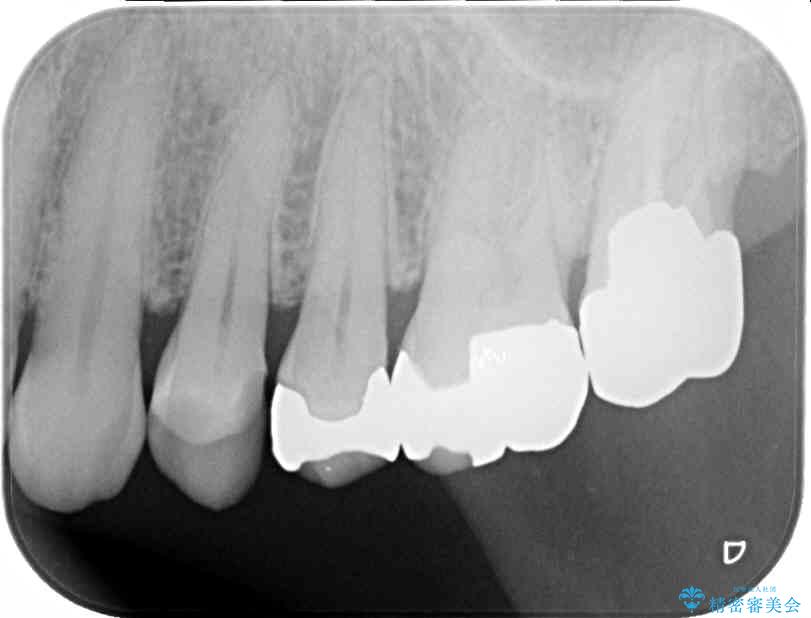

奥歯の銀歯が外れてしまったため、セラミック治療を希望された患者様です。

セラミックインレーによる修復治療を実施しました。

治療前

• 外れてしまった銀歯 セラミックインレーで自然な仕上がりに 治療前画像